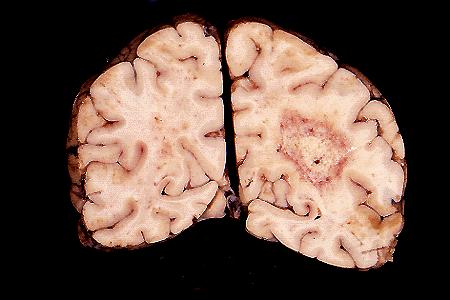

TORCH- cerebral toxoplasmosis

Toxoplasma encephalitis: a large lesion with central

necrosis